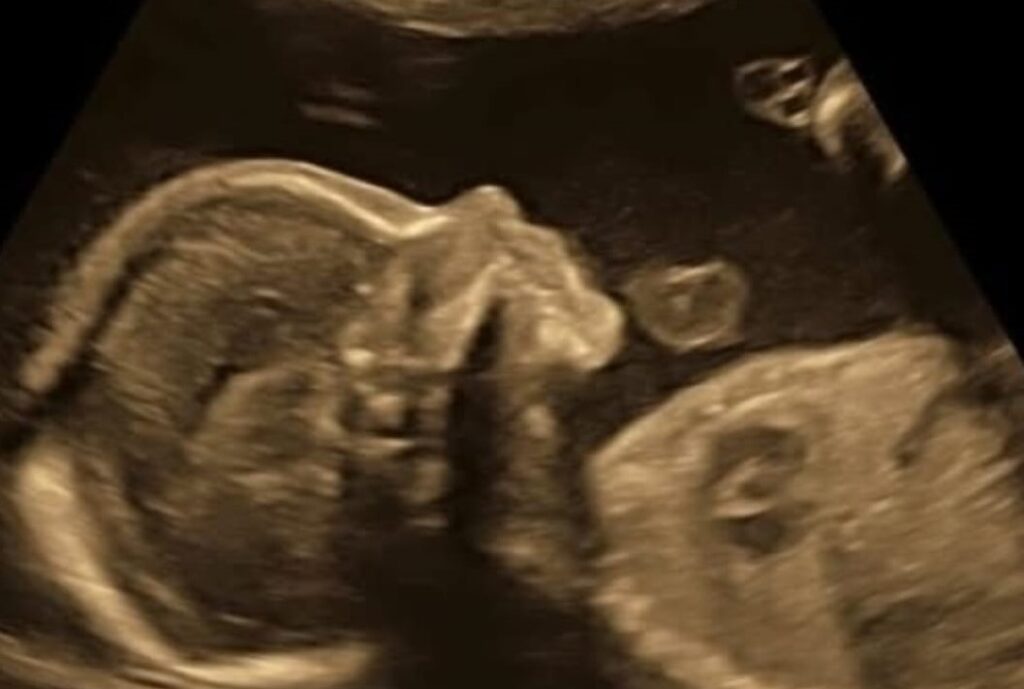

No entanto, a Anvisa respondeu que as restrições levam em consideração questões de segurança, pois a medicação pode causar efeitos adversos. “O misoprostol, principalmente quando utilizado sozinho, pode falhar” em 10% dos casos [imagem abaixo], segundo nota técnica assinada por especialistas da agência. “A gestação, então, pode vir a não ser interrompida e o feto ficar exposto a reações que ainda não são bem conhecidas”, continua.